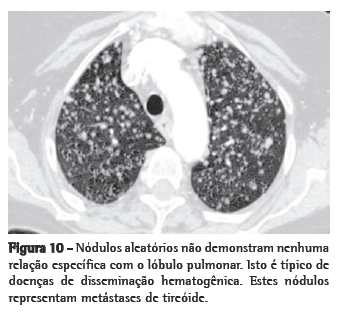

Random nodules

Random nodules are defined by their seemingly haphazard occurrence in

peribronchovascular regions, interlobular septa, and pleura, without a consistent perilymphatic pattern and absence of a consistent relationship with the secondary pulmonary lobule. An HRCT image from a patient with hematogenous metastases from thyroid cancer is shown in Figure 10.

Hematogenous metastasis

Hematogenous metastasis is the most common cause of multiple randomly distributed pulmonary nodules. Basilar predominance is typical, due to preferential blood flow to the lung bases. Since the malignant cells enter the pulmonary lymphatics, features of lymphangitic carcinomatosis with irregularly thickened interlobular septa and pleural effusion are common. In surgical lung biopsies, irregular nodules of endovascular and endolymphatic tumor are present (Figure 3).

Although the appearance of miliary nodules has many causes, the most common are metastasis, tuberculosis, fungal infections, and sarcoidosis.(47) Miliary metastasis are frequently due to thyroid cancer, renal cancer, melanoma, or other malignancies, whereas larger and less profuse metastases tend to be adenocarcinomas in adults, typically originating from the lung, breast, or gastrointestinal tract.